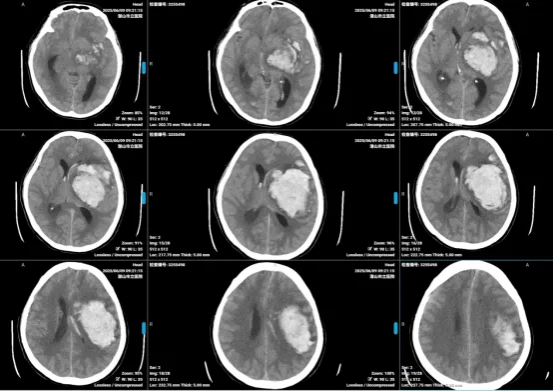

患者女,60歲,因“突發(fā)意識障礙1小時”入院。入院時神志深昏迷,GCS3分(E1V1M1),兩瞳孔不等大,直徑左:右=4mm:2.5mm,對光反射均遲鈍,頭顱CT顯示左側(cè)基底節(jié)區(qū)-額頂頂葉腦出血,出血量約110mL。